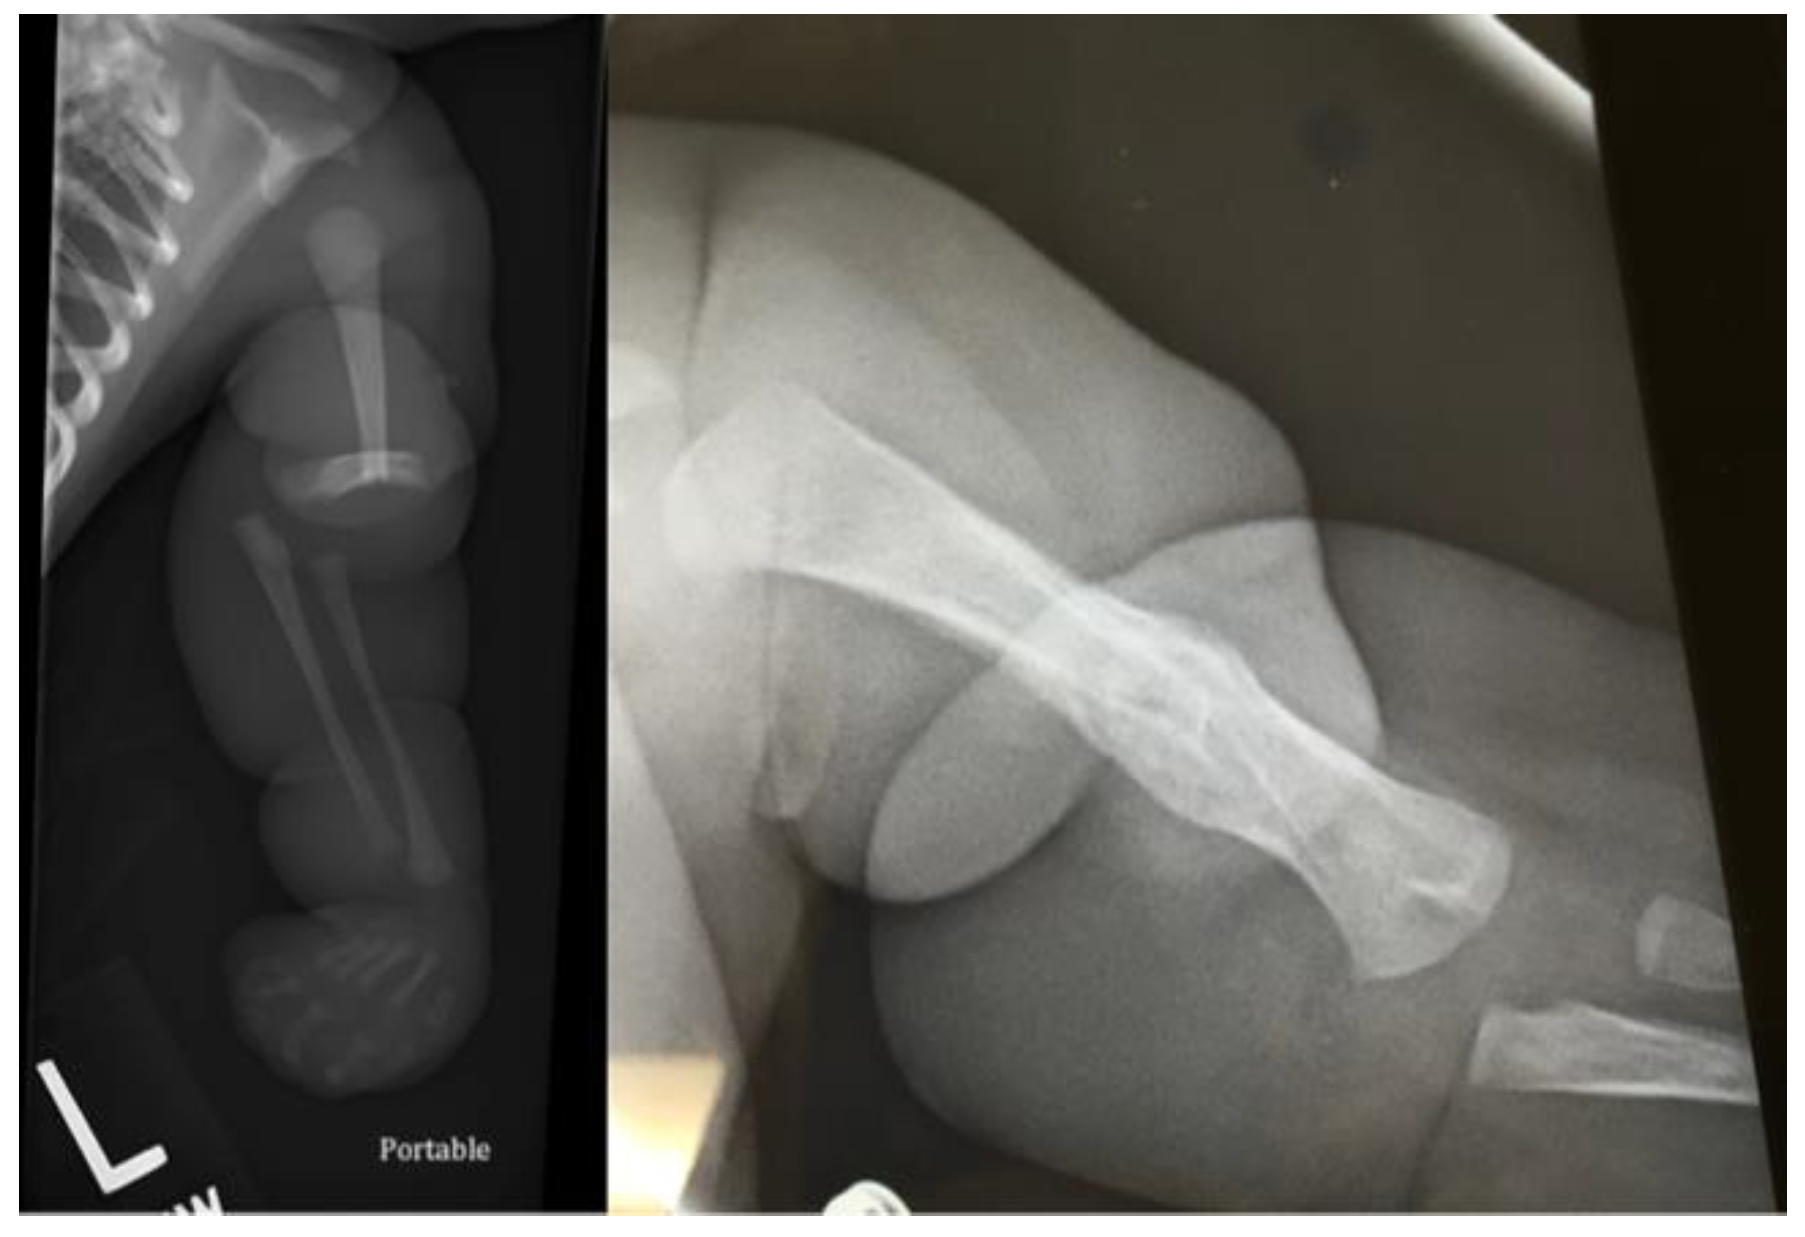

Fractures in the Setting of Constriction Band Syndrome: A Case Series of Three Patients with Extremity Fractures at the Site of a Constriction Band

2. Case Presentation